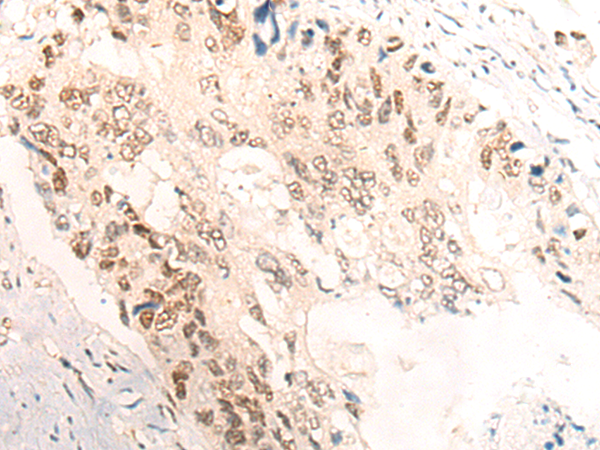

分类: 科研抗体货号: P12437别名: AIRAP应用: WB,IHC反应种属: Human